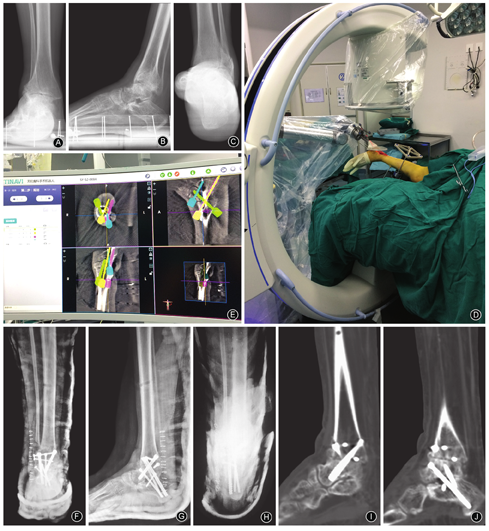

患者,女,59岁,因"双侧马蹄内翻足矫正术后20年,右踝关节疼痛2年"入院。患者因脊髓灰质炎后遗症致双侧马蹄内翻足,20年前手术矫正,具体不详,效果满意。2年前,患者无明显诱因出现右踝关节疼痛,行走时明显,不平路面行走时显著,且症状进行性加重。入院查体示右踝关节轻度内翻畸形,外踝以及下方广泛压痛,背伸活动度0°、跖屈30°、距下关节内翻0°、外翻5°,美国足踝外科协会(American Orthopaedic Foot and Ankle Society,AOFAS)评分28分,视觉模拟评分(visual analogue scale,VAS)在负重行走时为9分,非负重活动时为4分。双侧踝关节负重正、侧位X线片及后足负重力线X线片示右侧胫距关节间隙狭窄,力线异常,距下关节硬化(图1A,图1B,图1C)。诊断:右侧踝关节骨关节炎、距下关节炎。患者入院后完善检查,排除手术禁忌证后行机器人辅助下胫距跟关节融合术。

患者侧卧位,取外侧纵行切口,外踝截骨,暴露胫距关节以及距下关节,清理骨赘,去除关节面软骨,处理松质骨床,调节力线至满意后,克氏针临时固定;"C"型臂X线机透视下确认力线满意后,以外固定架临时固定胫骨,将小腿放置于合适位置,示踪器固定于外固定架针上,以辅助机器人"C"型臂行术中CT透视(图1D)。

采集图像后,于机器人系统内行4枚无头加压螺钉置钉规划,其中2枚交叉螺钉由胫骨远端前方至跟骨后结节,1枚螺钉自距骨颈至跟骨后结节,1枚螺钉自胫骨远端后方至距骨头,规划每枚螺钉的大小、方向以及长度(图1E)。在机器人系统机械臂瞄准辅助下经皮依次置入规划的螺钉,"C"型臂透视下确认螺钉位置是否满意。纵劈截下的远段腓骨,将外侧部分作为骨板并以3枚普通螺钉固定于胫骨、距骨及跟骨,冲洗后缝合伤口。

术后患者复苏后未出现神经损伤症状;X线及CT检查示胫距关节无头加压螺钉位于距骨头,胫、距、跟骨通过4根交叉无头加压螺钉固定,置钉位置远端位于跟骨结节附近,内固定位置满意(图1F,图1G,图1H,图1I,图1J)。